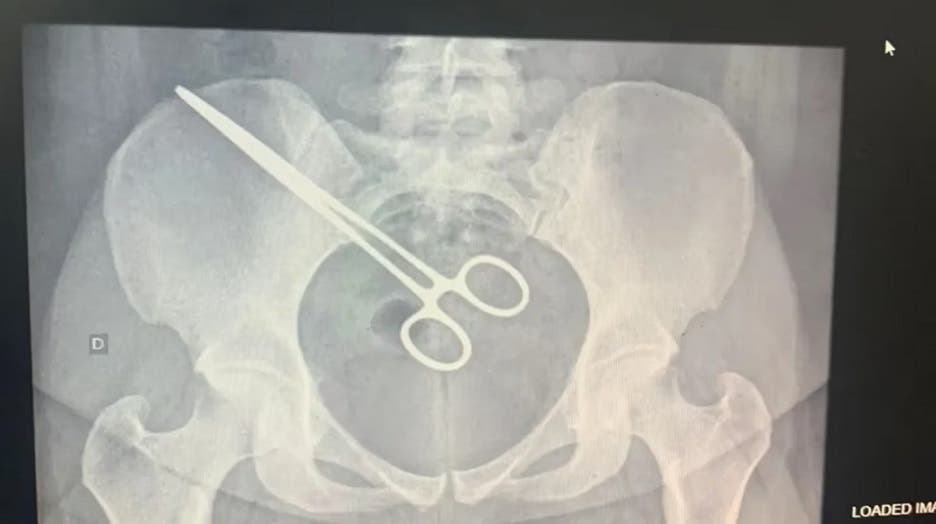

En Brasil, una mujer 27 años descubrió que había unos fórceps quirúrgicos dentro de su cuerpo cuando pasaba por un detector de metales de la prisión en la que se encuentra detenido su marido.

Cuando se presentó en el Centro de Detención Provisional de São José do Rio Preto, San Pablo, se percató que había unas tijeras en la región pélvica de su organismo.

Luego del episodio, la paciente acudió al hospital Santa Casa, donde le hicieron un examen de rayos X y encontraron que la pinza estaba dentro de ella.